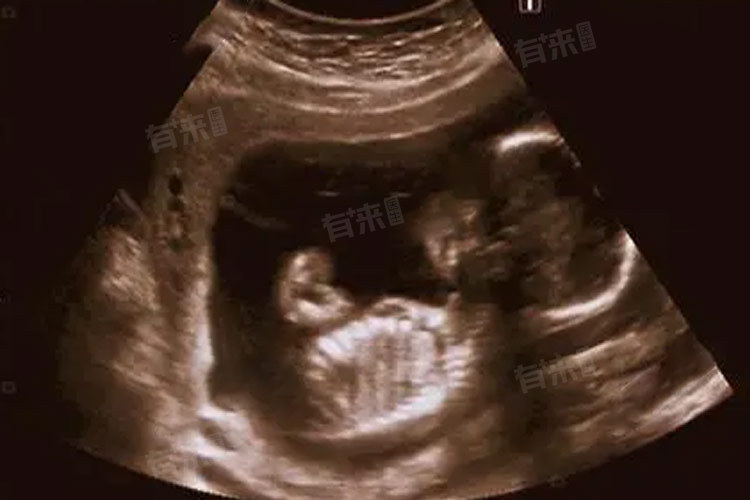

在彩超图像上,三个月的胎儿初具人形,从头到臀的长度在7-9厘米。头部相对较大,几乎占据了整个身体的一半,大脑在这个阶段发育迅速,不同部位可以观察到不同表现,包括头颅与面部、心脏与循环系统等。

- 头颅:通过彩超可以清晰看到胎儿的头颅轮廓,呈圆形且完整,颅骨光环显示清晰,这表明胎儿的颅骨发育正常。此时医生还能测量胎儿的双顶径,即头部左右两侧之间最宽部位的长度,这是评估胎儿发育的重要指标之一。一般来说,三个月胎儿的双顶径平均值在2.52厘米左右。

- 面部:胎儿的眼睛、鼻子、嘴巴等面部特征逐渐显现。虽然还不够清晰,但已经能分辨出眼睛的位置,小小的鼻孔也能隐约看到,嘴巴有时会呈现出微微张开的状态。

- 心脏:胎儿的心脏在这个阶段已经发育成四腔结构,左右心房和左右心室清晰可辨。彩超下能看到心脏有规律地跳动。

- 脊柱:胎儿的脊柱在彩超下呈一条连续的、规则的强回声带,从颈部一直延伸到骶尾部。这表明胎儿的脊柱发育良好,没有出现脊柱裂等异常情况。

- 四肢:可以清楚地看到胎儿的上肢和下肢,手臂和腿部的骨骼已经形成,能分辨出上臂、前臂、大腿和小腿。手指和脚趾也开始分化,虽然还比较小,但已经能看到大致形态。